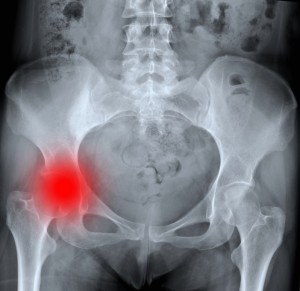

Симптомы заболевания зависят от стадии и длительности протекания заболевания. Но основным проявлением коксартроза является боль в суставе при нагрузке, которая отдает в пах и прекращается в покое. Различают 3 степени заболевания.

- При 2-й степени коксартроза в процесс вовлекаются костные структуры, возникают костные разрастания, деформация головки бедренной кости, начинают формироваться кисты. Боль при ходьбе становится значительной, человек начинает щадить больную ногу при ходьбе, тем самым нагружая здоровую.

- При 3-ей степени коксартроза преобладают разрастания костной ткани, формируются образования, которые вызывают болевые ощущения и в покое. На этой стадии также возникают переломы, так как костная ткань сустава перестает быть состоятельной.